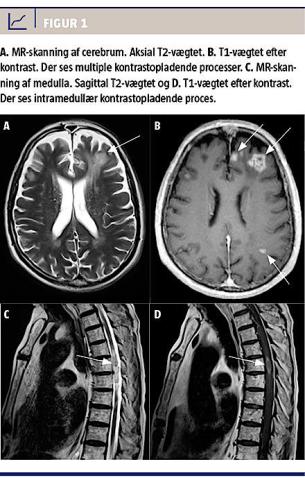

Han blev overflyttet til et andet sygehus pga. tiltagende konfusion og tværsnitssymptomer med spastisk paraparese og sfinkterpåvirkning. En MR-skanning af columna totalis viste en intramedullær proces ud for Th5 med central blødning, let perifokalt ødem og kraftig kontrastopladning (Figur 1).

CT og MR-skanning af cerebrum med kontrast viste multiple kontrastopladende læsioner og der blev overvejet følgende diagnoser: infektion/abscesser, cerebrale metastaser eller lymfom. Spinalvæsken indeholdt 9 × 106/l, 88% lymfocytter, heraf 15% B-lymfocytter med svag overvægt af kappa, hvilket dog ikke var sikkert diagnostisk. Der blev målt svært forhøjet proteinniveau på 2,52 g/l. Spinalvæske- og serumprøver var negative for toksoplasmose, cytomegalovirus og Aspergillus.

Diagnosen PTLD blev i dette tilfælde stillet på baggrund af histologisk undersøgelse af tumorvæv fra medulla, hvor der blev påvist et EBV-associeret, højmalignt diffust storcellet B-cellelymfom fire år efter en nyretransplantation. PTLD med intramedullær involvering er en usædvanlig komplikation hos immunsupprimerede, transplanterede patienter [3, 4]. MR-skanning er den bedste metode til påvisning af patologiske forandringer i CNS, specielt i spinalkanalen.

Den typiske medullærlæsion opstår hyppigst cervikalt og ses på MR-skanningsbilleder som velafgrænset og hyperintens på T2-vægtet skanning og som kraftig kontrastopladende på T1-vægtet skanning. Eventuelt ses der også central blødning [5].